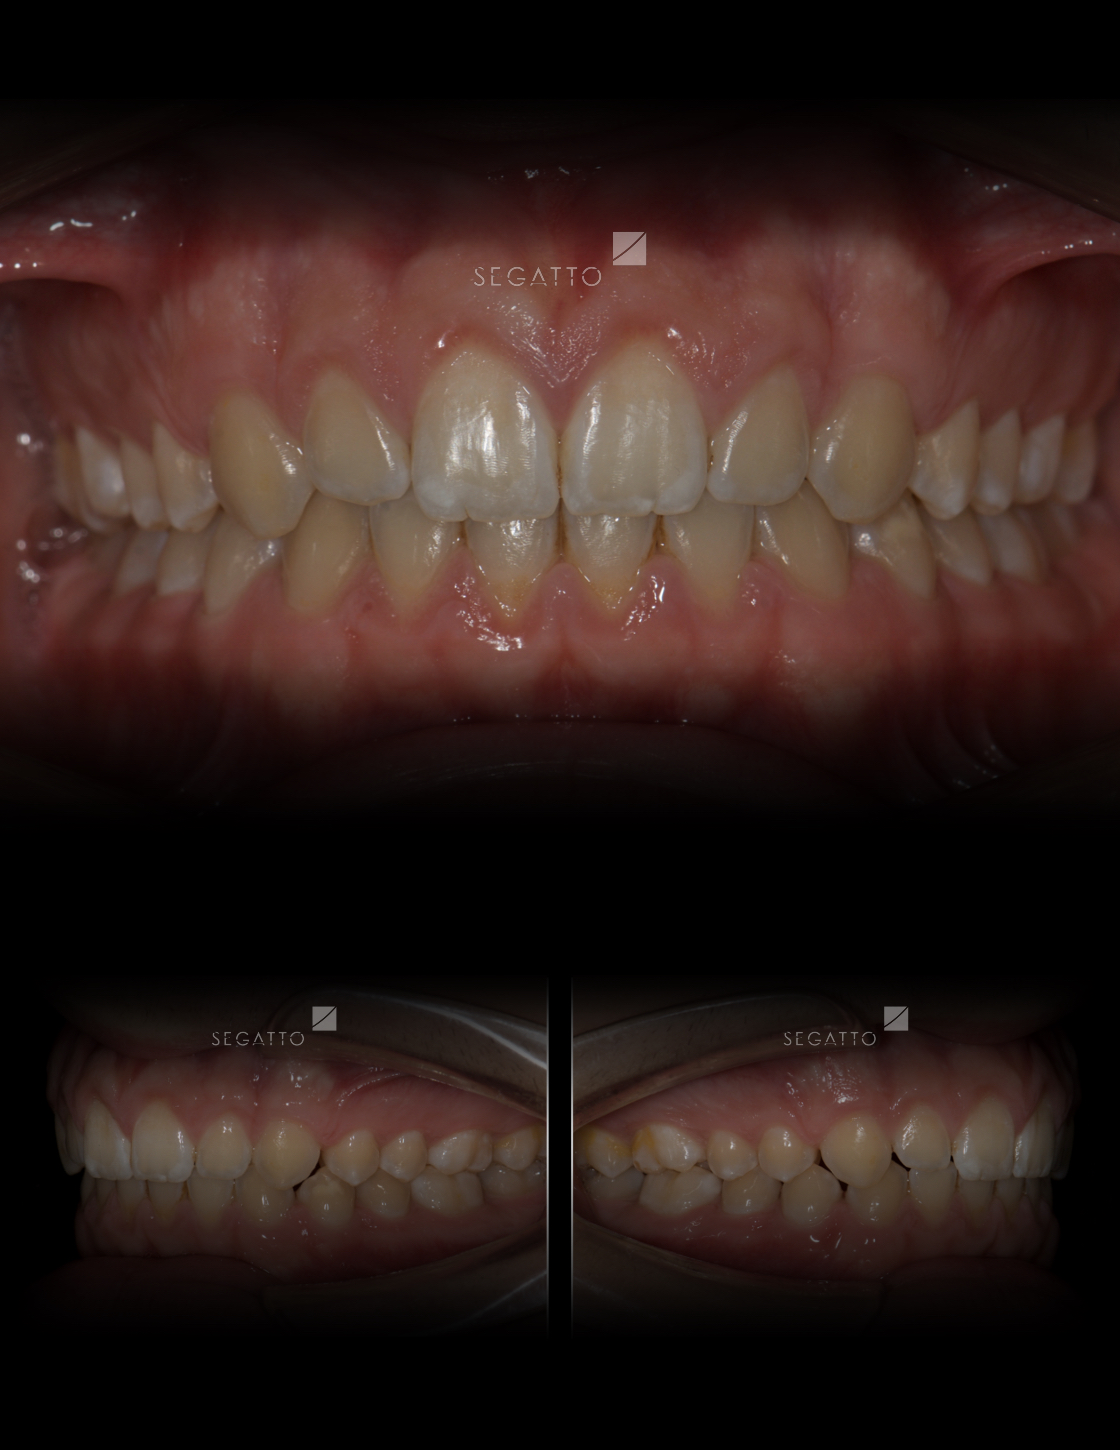

Orthodontics

Cases